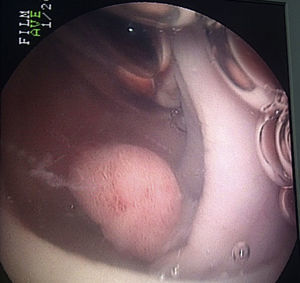

No se presentaron complicaciones en ningún grupo (tabla 6). El diagnóstico endoscópico más frecuentemente encontrado fue hemorroides (21 y 35%, respectivamente) seguido de enfermedad diverticular (15 y 26%) y pólipos (8 y 29%) (figs. 1 y 2). El 4% de los pacientes a los cuales se les realizó la colonoscopia mediante la técnica de inmersión tuvieron un estudio normal y el 6% de los pacientes estudiados con la técnica por insuflación también según tabla 7.

Los pólipos tuvieron una localización predominante en el colon descendente y colon sigmoides mientras que los divertículos tuvieron en mayor proporción su ubicación en el colon sigmoides para ambos grupos (32 y 16%, respectivamente).